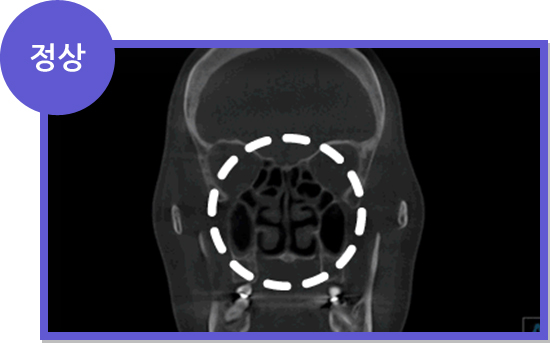

CT

CT

세계적으로 인정받는

Amorphous Silicon Flat Panel

센서를 사용하여 선명한 고화질로

환자의 상태를 볼 수 있어

정확한 진단이 가능한 CT로 진단

세계적으로 인정받는

Amorphous Silicon Flat Panel

센서를 사용하여 선명한 고화질로

환자의 상태를 볼 수 있어

정확한 진단이 가능한 CT로 진단